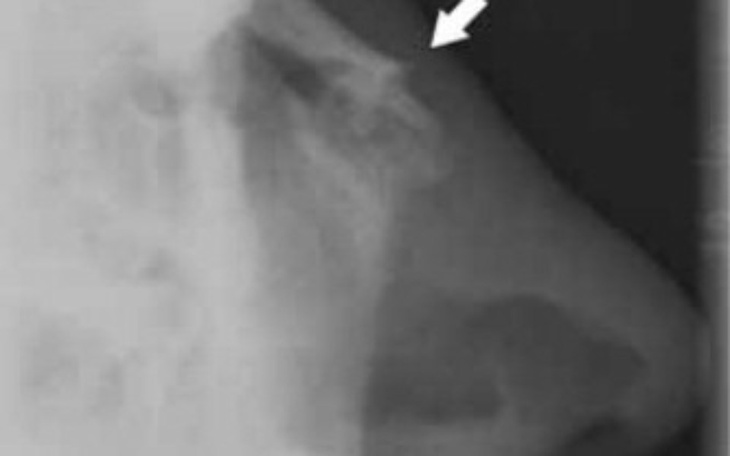

Mam na imię Kinga , mam 23 lata. Rok temu a dokładnie 18 lutego 2023 miałam wypadek samochodowy, czołowy w wyniku czego doznałam kilku poważnych złamań oraz zwichnięć , m.in. złamania nosa z przemieszczeniem się odłamku kości, złamania dwóch żeber, wstrząsu mózgu, obitych płuc , złamaniu prawej ręki , złamaniu kręgu szyjnego C7 , oraz doznałam kilku poważnych rozcięć twarzy przez co widnieją na mojej twarzy większe , wgłębione blizny których nie udało się usunąć. Przechodzę ciężką rehabilitację , lecz niestety na NFZ nie jest łatwo o bliski termin wizyt do potrzebnych mi specjalistów. Dwa razy w miesiącu chodzę także prywatnie na wizyty do psychologa ponieważ ciężko uporać mi się z tym , dlaczego to musiałam być ja , dlaczego ten człowiek mi to zrobił skoro jechałam zgodnie z przepisami . W tym wszystkim najbardziej dokuczają mi skutki po złamaniu nosa oraz złamaniu kręgu szyjnego przez co nie mogę wykonywać swojej dotychczasowej pracy . Nos bardzo boli ,w niektórych przypadkach leki przeciwbólowe nie pomagają , nos robi się często obrzęknięty , tkliwy i często sączy się z niego krew. Niestety nie kwalifikuję się do operacji na NFZ ponieważ popełniono błąd w szpitalu ,przez co nie udało mi się wygrać z nimi sprawy sądowej bo nie przyznano się do popełnionej winy. Chcę aby wszystko wróciło już do normy ,żebym mogła uciec na stałe od bólu i zmartwień które mi towarzyszą . 2/3 pieniędzy udało mi się odłożyć gdy jeszcze pracowałam ale nie zdołam uzbierać reszty kwoty, dlatego liczę na wasze wsparcie , na waszą pomoc. Dziękuje także wszystkim którzy przekazali mi choć jeden procent, każdy grosz to dla mnie wiele.